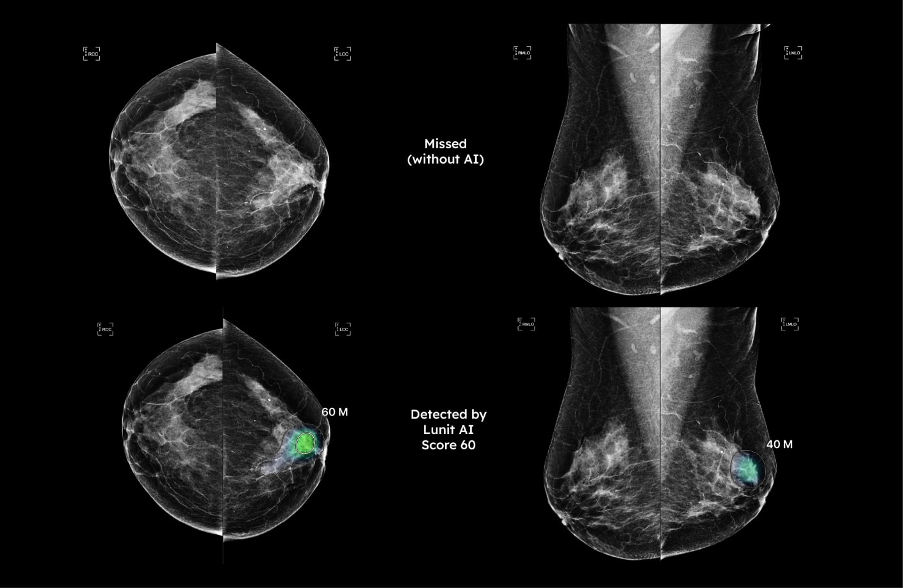

AI tầm soát ung thư vú ứng dụng trong quy trình chụp X-Quang tuyến vú, đã được FDA cấp phép lưu hành theo mã K211678 và đạt chứng nhận tiêu chuẩn châu Âu CE, có khả năng nhận diện chính xác lên đến 97% đối với các tổn thương có kích thước rất nhỏ (từ 2mm) mà mắt thường dễ bỏ sót trong môi trường đọc phim tiêu chuẩn, có khả năng phát hiện các tổn thương ung thư ở thể không tạo khối - dạng tổn thương cực kỳ khó nhận biết trên phim X-quang thông thường, thường là nguyên nhân dẫn đến các trường hợp âm tính giả (bỏ sót bệnh).